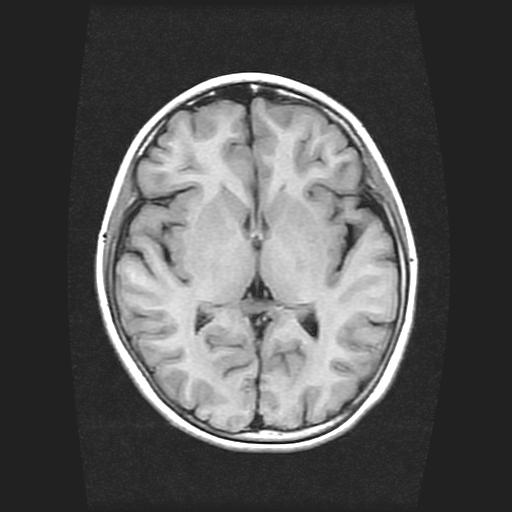

标题: PED0378:女孩9岁,癫痫,看能否停药 [打印本页]

9岁女孩,三岁时诊断为癫痫,一直服丙戊酸钠,现患者一般情况良好,家长复查核磁片,看能否停药..

巨脑回